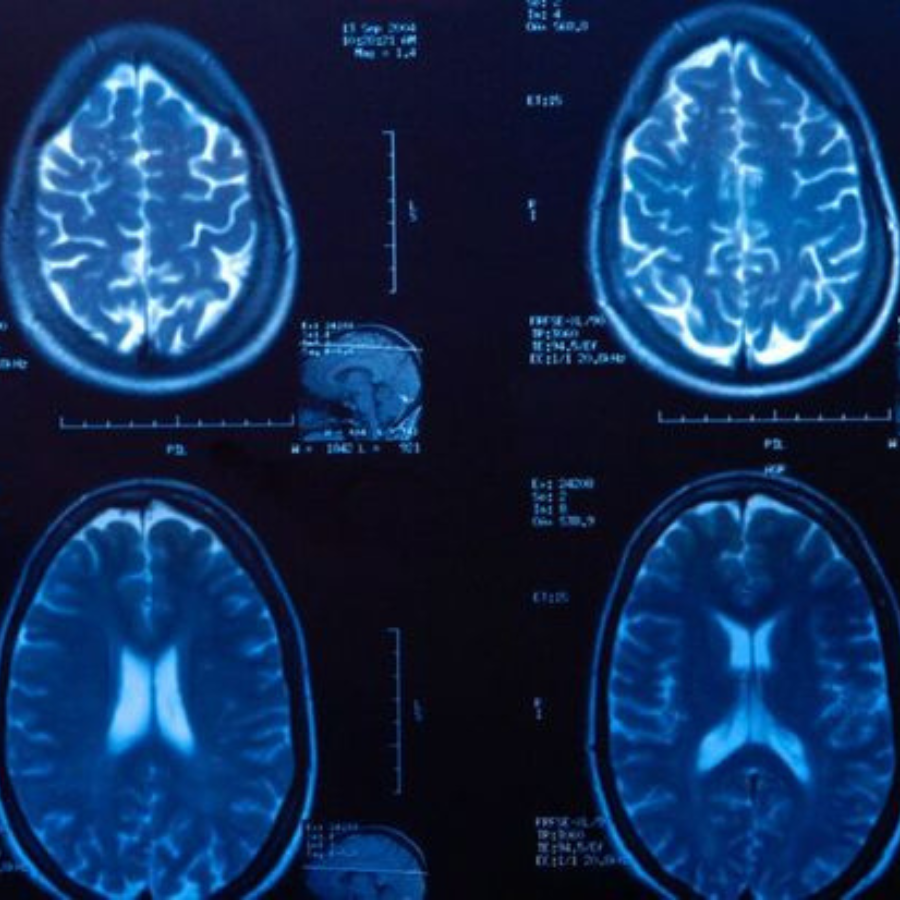

Parkinson’s disease is a progressive disorder of the nervous system in which certain brain cells gradually lose the ability to produce dopamine. Dopamine is a chemical that helps control movement and coordination. As dopamine levels fall, people with Parkinson’s experience tremors, stiffness, and slowed physical responses.